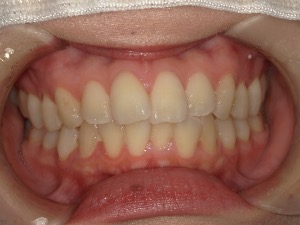

after

患者さんの年齢 20代 女性 症状 ガタガタを治したい 治療内容 マウスピース矯正治療 費用 90万(税抜) 治療期間・回数 治療期間2年、通院回数10回 メリット 笑顔が綺麗 デメリット・リスク 期間がかかることがある - マウスピース矯正